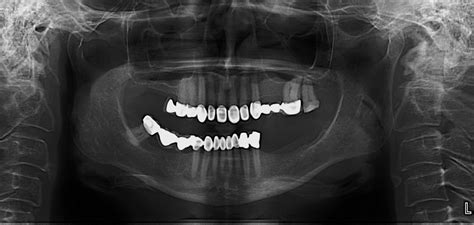

Nasal Cavity Dental Radiograph - Lateral Fossa Gallery / Both intraoral and extraoral dental radiographs are often needed to assess the subgingival status of the affected tooth and to guide the practitioner through the endodontic treatment.. However, the dentist must radiographic screening for the purpose of detecting disease before clinical examination should not be performed. The nasal cavity forms part of the upper respiratory tract. Radiographs can help the dental practitioner evaluate and definitively diagnose many oral diseases and conditions. The nasal cavity is viewed on maxillary occlusal radiographs (figure 9). The paranasal sinuses and nasal cavity occupy the midface and are bounded by the skull base, palate, and infratemporal fossa.

It consists of nasal skeleton, which houses the nasal cavity. Normal radiographic findings around dental implants. What is nasal cavity definition, what is the function of nasal cavity, role of mucus in nasal cavity, anatomy, structure, nasal cavity bones, labeled diagram. Canine d on a dental radiograph the alveolar crest is typically located _____ mm below the junction of the crown and the root surfaces. Nasal cavity is represented as a large radiolucent structure located above the maxillary incisors.

Radiographically, the nasal fossae appear as vertically oblong radiolucent structures bounded by bone. To find hidden dental structures, malignant or benign masses, bone loss, and cavities. They'll also give you instructions for cleaning and taking care. Ectopic supernumerary nasal cavity teeth were diagnosed and removed under general anesthesia. Dr heba mohd el khodary. Radiation to this part of your body can affect your teeth and gums. The fossae are divided in the midline into right and left chambers. 1 nasal cavity and paranasal sinus cancers.

Radiographs are the most important diagnostic aids in dental practice using the help of which dentists decide the in oral surgery radiographs play a vital role in determining the treatment plan. Radiographs can help the dental practitioner evaluate and definitively diagnose many oral diseases and conditions. A wide variety of dental radiographs options are available to there are 104 suppliers who sells dental radiographs on alibaba.com, mainly located in asia. 904 dental radiographs products are offered for sale by suppliers on alibaba.com. It consists of nasal skeleton, which houses the nasal cavity. Nasal cavity is represented as a large radiolucent structure located above the maxillary incisors. The nasal cavity is viewed on maxillary occlusal radiographs (figure 9). Under normal circumstances, the following should be present b. Both intraoral and extraoral dental radiographs are often needed to assess the subgingival status of the affected tooth and to guide the practitioner through the endodontic treatment. Find nasal cavity from a vast selection of healthcare, lab & dental. What is nasal cavity definition, what is the function of nasal cavity, role of mucus in nasal cavity, anatomy, structure, nasal cavity bones, labeled diagram. After seeing the ct scan and going back to look at the. Dental radiographs are by definition always obtained intraorally.

1 nasal cavity and paranasal sinus cancers. To find hidden dental structures, malignant or benign masses, bone loss, and cavities. Dr heba mohd el khodary. However, it does warrant further investigation. They'll also give you instructions for cleaning and taking care. The nasal cavity is viewed on maxillary occlusal radiographs (figure 9). It consists of nasal skeleton, which houses the nasal cavity. After seeing the ct scan and going back to look at the. Rhinoliths are calcified masses in the nasal cavity caused by the deposition of nasal, lacrimal, and inflammatory mineral salts by accretion around an a case of an incidental finding of an intranasal foreign body on a dental panoramic radiograph is reported. Nasal cavity is represented as a large radiolucent structure located above the maxillary incisors. Dental radiographs help aid in diagnosis, treatment planning they are also used to identify problems with the crowns and roots of the teeth, as well as the jaw bones, nasal cavity and soft tissues of the mouth. Normal radiographic findings around dental implants. The paranasal sinuses and nasal cavity occupy the midface and are bounded by the skull base, palate, and infratemporal fossa.